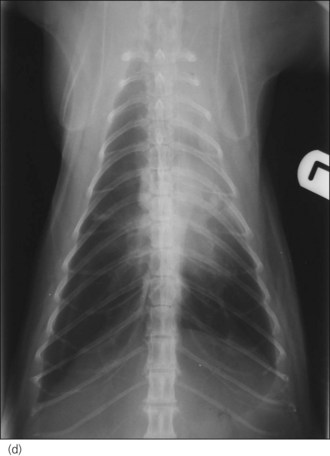

Figure 32.4 Right lateral and dorsoventral thoracic radiographs of a cat with idiopathic chylothorax (a, b) before and (c, d) after thoracocentesis. The post-drainage films were taken the day after under general anaesthesia; an oesophageal stethoscope is visible.